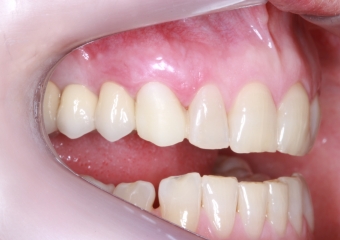

Foto lateral pré-cirurgica 03-10-16 - Clínica Cliniface

Foto lateral pré-cirurgica 03-10-16